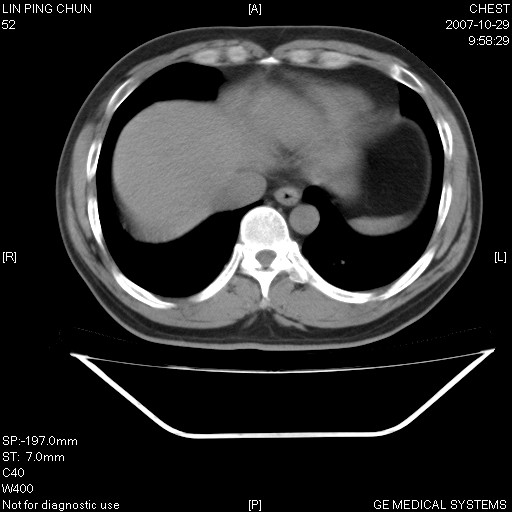

标题: CT10239:男,42Y.我自己的胸部CT扫描,今天10点突然咯血一次。

我自己胸部ct扫描,求助大家,我自己还不能给自己诊断。其他层面纵隔窗无异常。

补充:男,42y.今天10点突然咯血一次。余无异常。

左肺下叶后基底段小片结节状影,内部似见同心圆状分布条絮状影,整个病灶,质不实.局部见增粗血管影.

考虑;球形肺炎可能大.自已的身体如此重要,不进一步局部薄层及hrct?

左下肺后基底段磨玻璃样影,很多病都可以。不能吊以轻心。应该做局部增强hrct进一步检查,并严格抗炎治疗后复查或经皮活检。

左下肺后基底段小斑片泪膜玻璃样影,其内可见空泡影,边缘可见小毛刺影。建议抗炎治疗复查,肿瘤待排